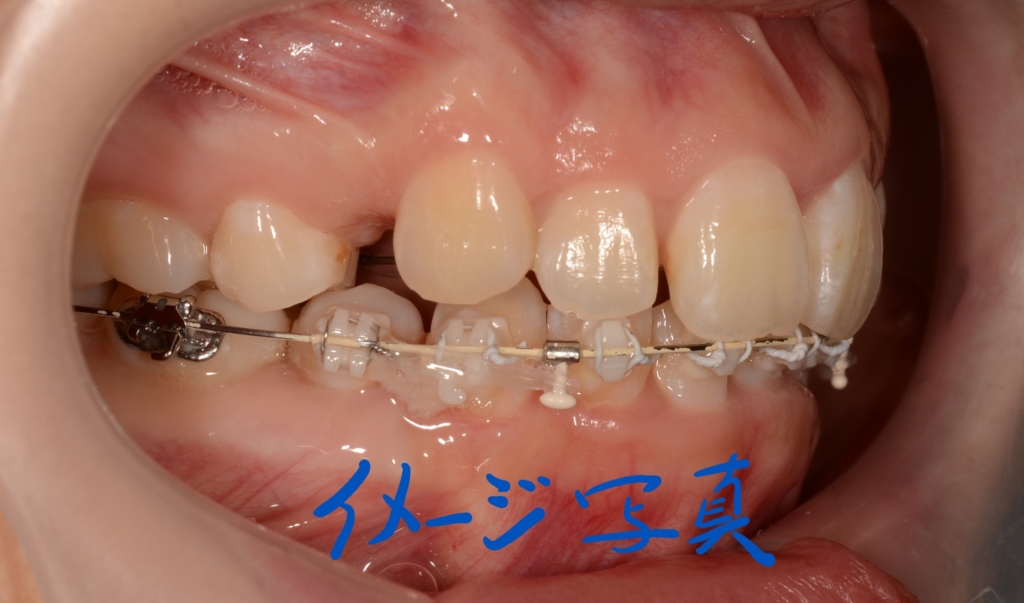

【治療装置】

マルチブラケットシステム(ハーフリンガル type)で矯正を開始。

途中、早期の被蓋改善を図るため、上の奥歯から下の前歯へ引っ掛ける顎間ゴムを3か月間使用しています。